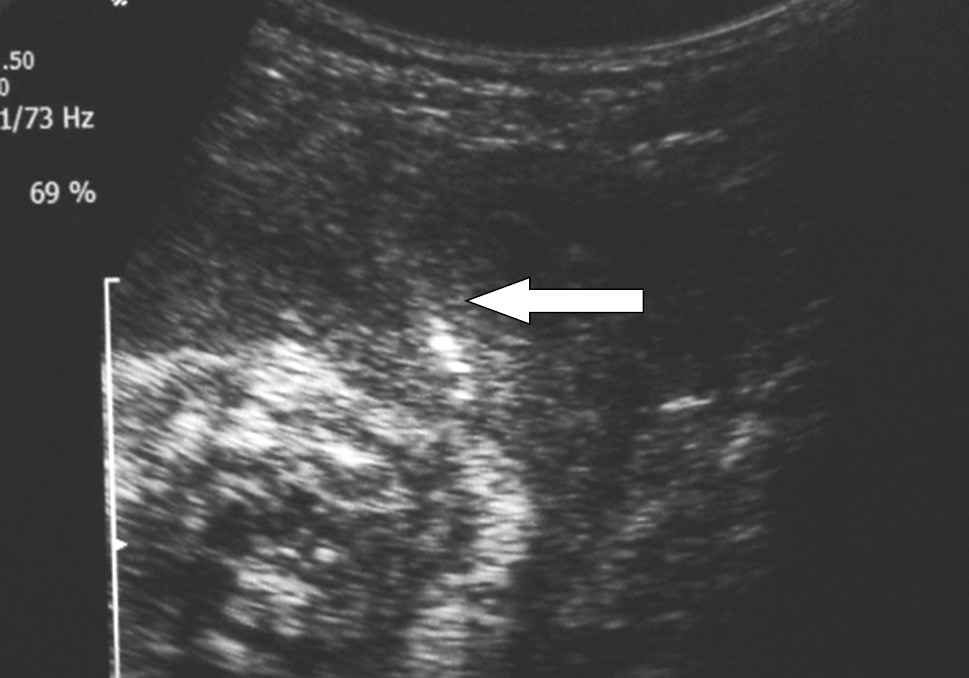

ФГБУ «НИИ ОММ» МЗ РФ Екатеринбурга обладает собственным опытом применения НТАИ с использованием имплантируемой подкожной порт-системы. В 2014 г. данный метод был апробирован на экспериментальных животных (овцах), затем внедрен в клиническую практику [26]. Пациентке Ю., история родов № 2370, была проведена НТАИ. Возраст женщины — 28 лет, пациентка имела отягощенный акушерский анамнез: первые срочные роды без осложнений, затем два самопроизвольных выкидыша (в 8 и 22 нед.), две неразвивающиеся беременности в 6 нед. Соматический статус пациентки характеризовался наличием пролапса митрального клапана, дефицитом массы тела 15,0 %, артериальной гипертензией 2-й степени. На диспансерном учете при данной беременности состояла с ранних сроков. Беременная поступила в приемное отделение ФГБУ «НИИ ОММ» МЗ РФ в сроке 27–28 нед. с ПИОВ. При обследовании выявлено выраженное маловодие: по УЗИ амниотический индекс менее 3 см. После коллегиального обсуждения и получения информированного согласия пациентки было решено прибегнуть к установке порт-системы с целью проведения длительной амниоинфузии (рис. 1).

Рис. 2. Проводник в амниотической полости [26]

Fig. 2. Conductor in the amniotic cavity [26]